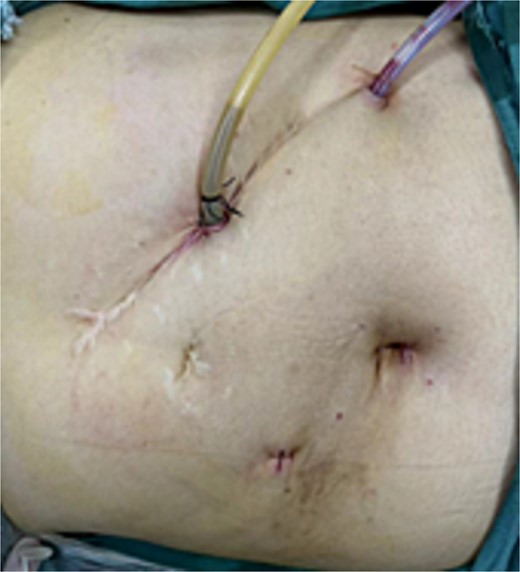

There is no consensus on the optimal positioning of the surgeon for SIT patients. Kigasawa et al. [3] successfully performed surgery with the lead surgeon standing on the right and the assistant on the left in a reversed position. Yaegashi et al. [4] also reported similar success with this approach, emphasizing the importance of adjusting the surgical team’s positions for SIT patients. In our case, severe adhesions in the upper abdomen, particularly on the left side, led us to select the right midclavicular line, 3 cm above the umbilicus, as the main working port. The original incision along the left midclavicular line under the costal margin was used as the secondary working port for T-tube placement and external drainage, while an additional port was placed along the left anterior axillary line for inserting the abdominal drain (Fig. 4). The surgical team employed a reversed setup, which facilitated the successful completion of the procedure.